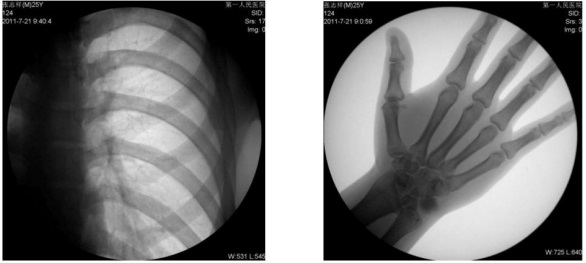

1、數(shù)字化透視:適用于全身各部位透視(如胸透、腹透等)。

動態(tài)采集速度≥25 幀/秒,主要應(yīng)用于臨床各科室,尤其是體檢科、內(nèi)科、外科、骨科、創(chuàng)傷科、急診科等。

1) 胸部檢查:能實現(xiàn)全胸透視動態(tài)觀察,對于需要在透視下動態(tài)觀察的病變,如肺部腫瘤、氣管異物等可進(jìn)行實時點片。胸部透視是體檢中的常規(guī)檢查項目,臨床意義在于檢查有無肺癌, 特別是早期肺癌。使用胃腸機(jī)可通過胸部透視雙肺,縱膈有無病變,以確定病變部位的部位、大小、密度,與周邊組織關(guān)系,常見的疾病,如肺炎、肺結(jié)核等。胃腸機(jī)可以從各種角度動態(tài)詳細(xì)觀察肺、心臟或其他胸部的病變,對病變的情況可以有個比較全面地了解。